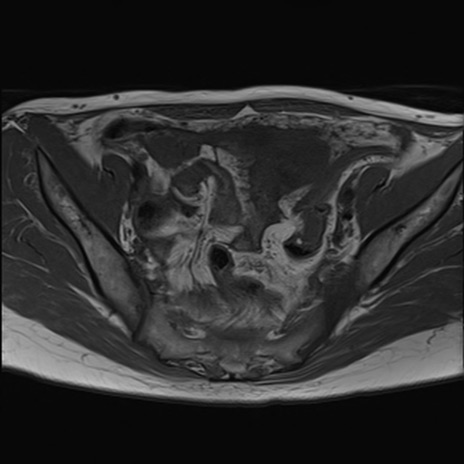

症例39 T1WI(横断像)

MRI(4日後)